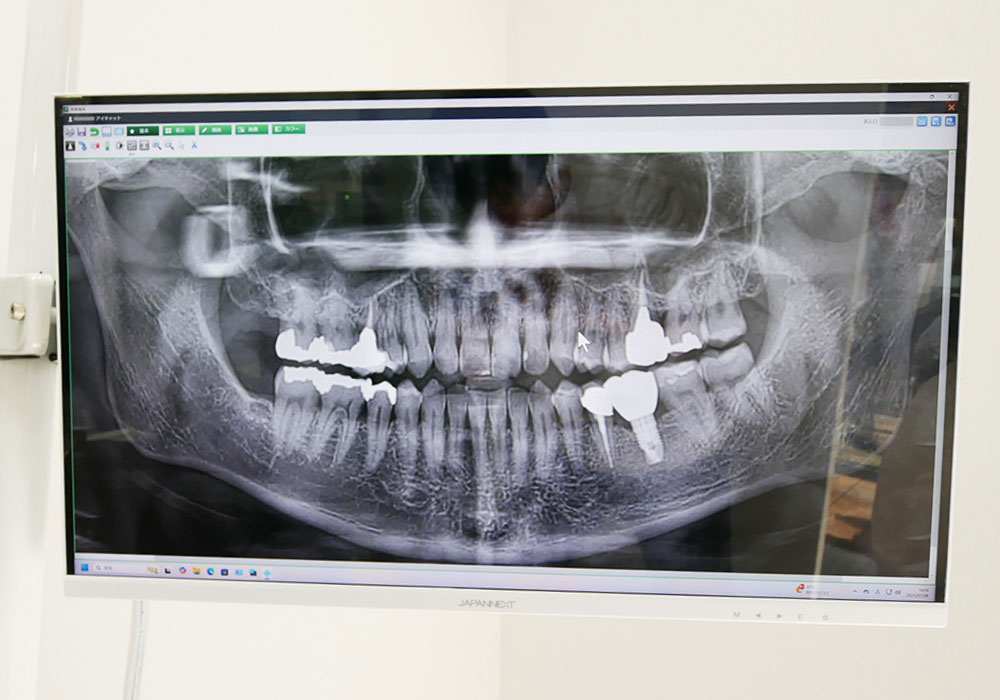

• 説明用モニター

説明用モニター

各診療台に設置しているモニター画面に、口腔内の画像やレントゲン写真を映し出します。患者さんや保護者の方もリアルタイムで画像を見ることができ、症状や治療の進行状況のわかりやすい説明に役立てています。